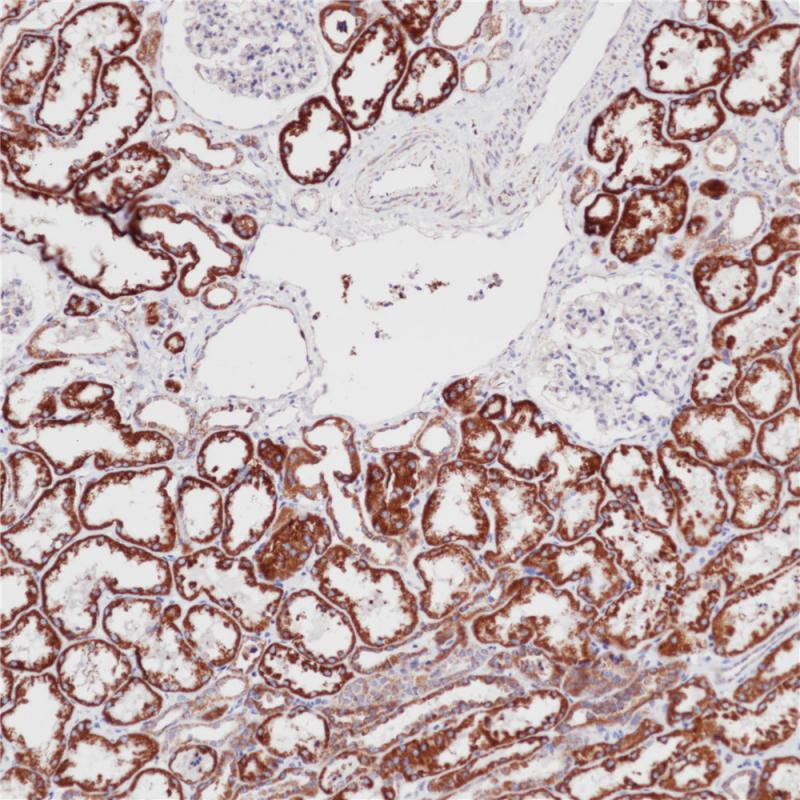

SDHB 重组兔单克隆抗体

琥珀酸脱氢酶 (Succinate dehydrogenase,SDH) 也称复合体 II 或琥珀酸:醌氧化还原酶,位于线粒体内膜,在三羧酸循环中可将琥珀酸转换成延胡索酸。SDH由4个亚基(A,B,C,D)组成,任何一个亚基发生突变将导致不稳定和复合体功能丧失。SDH各亚单位的突变均可导致SDHB蛋白缺失表达,故可用SDHB鉴定SDH缺陷型GIST。研究发现部分嗜铬细胞瘤(副节瘤)和肾细胞癌中存在SDHB突变。